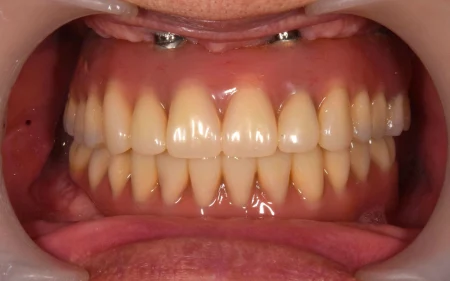

60代男性「歯がどんどん抜けて噛めない」連結した複数の人工歯をインプラントで支える「All on 4」で噛み合わせを改善させ、しっかり噛めるようにした症例

All on 4は、上顎に6本、下顎に4本埋め込んだインプラントで連結した複数の人工歯を支え、取り外しの必要がなくしっかり噛むことができて、見た目も綺麗に仕上がります。

上下ともに噛み合わせが安定し、お口全体でしっかり噛めるようになりました。

All-on-4は固定性のインプラントブリッジのため、ご自身で取り外しをすることなくお使いいただけます。